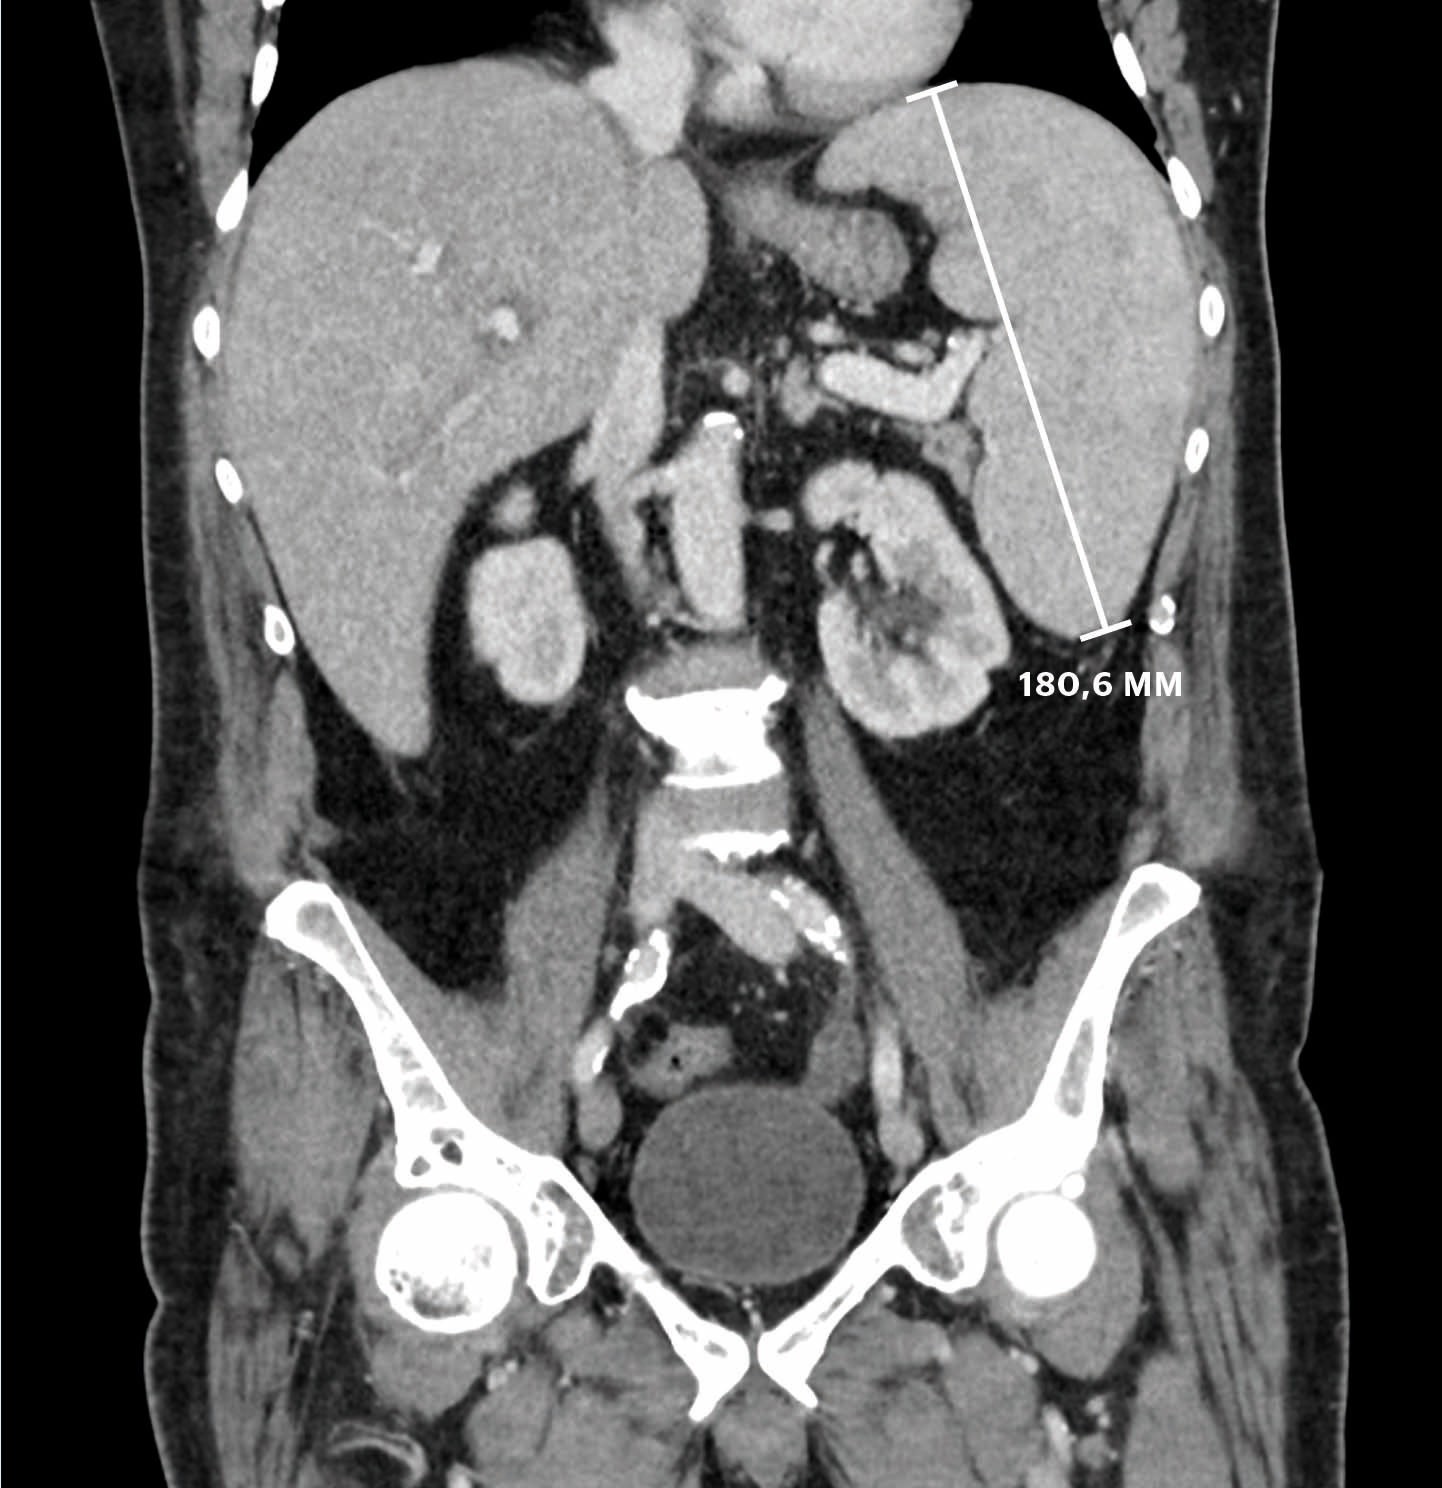

The patient was referred for MRI of the liver to look for microabscesses, which can be seen with systemic candidiasis. MRI of the liver on day 12 revealed no abscesses, but a possible splenic infarction. To clarify this, CT thorax/abdomen/pelvis was taken with contrast on day 13. The images confirmed splenic infarction and an increase in the size of the spleen to 18 cm (Fig. 1). His liver was enlarged, though this was not commented upon in the primary description. Splenic infarction aroused suspicion of endocarditis. A clinical examination on day 13 revealed no murmur or endocarditis stigmata. A transthoracic echocardiogram on day 15 showed no evidence of endocarditis. On day 21 antibiotic therapy was stopped to increase the chances of positive blood cultures. To exclude the possibility of infection, a total of 28 sets of 4 bottles were taken during his hospital stay. There was no growth of either fungi or bacteria in these cultures.

Figure 1 CT taken on day 13 showed an enlarged spleen (18 cm) and liver.